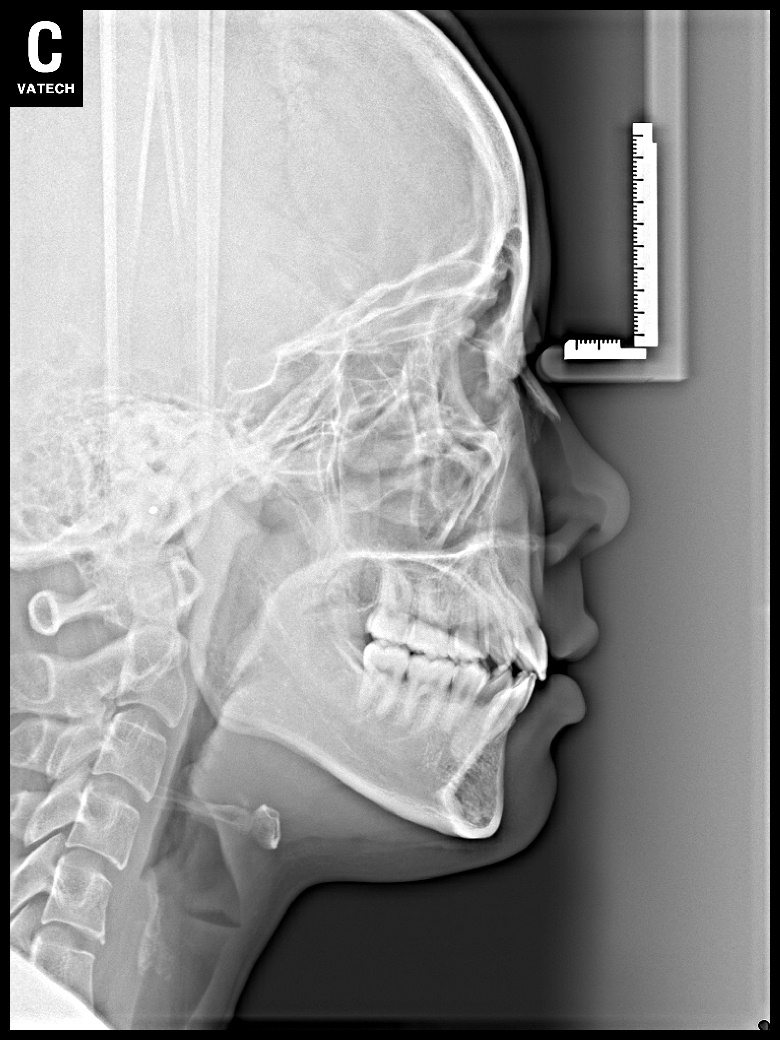

치료 후 사진입니다.